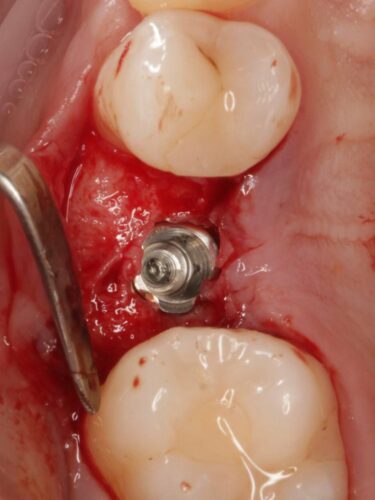

Установка импланта, подшит трансплантат с бугра( для увеличения объема мягких тканей), установлен формирователь десны

Установка импланта